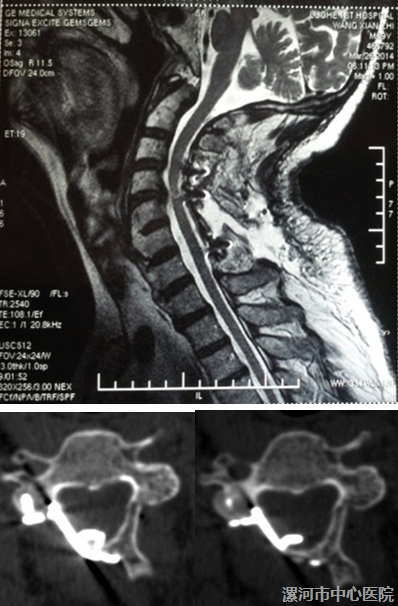

市创新性科研团队(脊柱科团队)设计了“保留颈2、3棘突肌肉止点的颈椎管成型术”。2008年以来,采用该创新型术式治疗 临床上较为多见的颈4~颈7狭窄的CSM。

只显露颈4~7的椎板,从而不切断附着在颈2、3棘突上的SSC,颈3椎板下半部潜行切除、胸1椎板上半部切除、颈4~7单开门

这样减压长度仍为5个节段(短了不利于脊髓后移),又较为完整的保留了 重要的SSC。

应用超声骨刀行保留颈半棘肌止点的新式手术